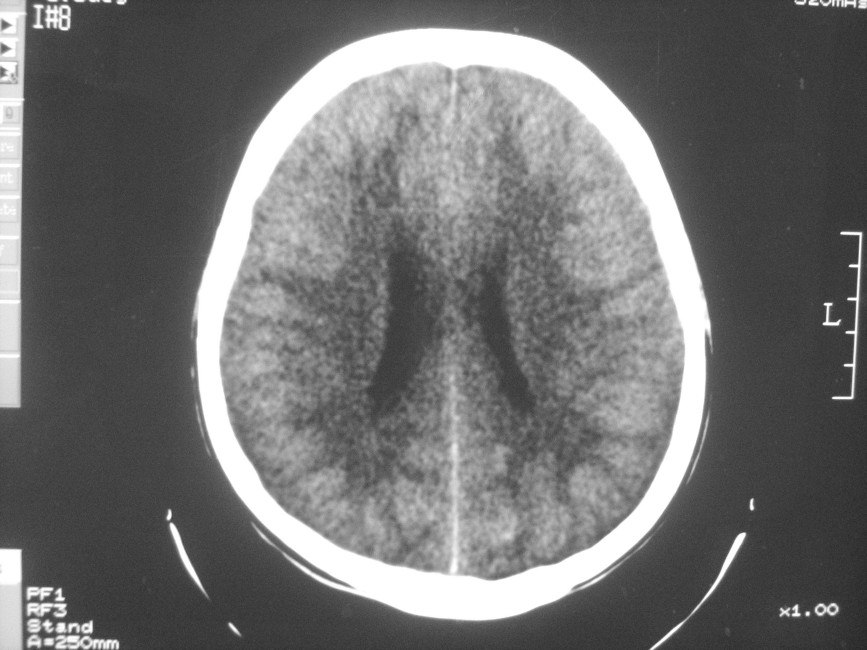

以下是引用zzyy在2008-6-16 10:13:00的发言:[br]两侧脑白质呈对称性密度减低,病儿有发热及脑膜刺激征。考虑急性病毒性脑炎。